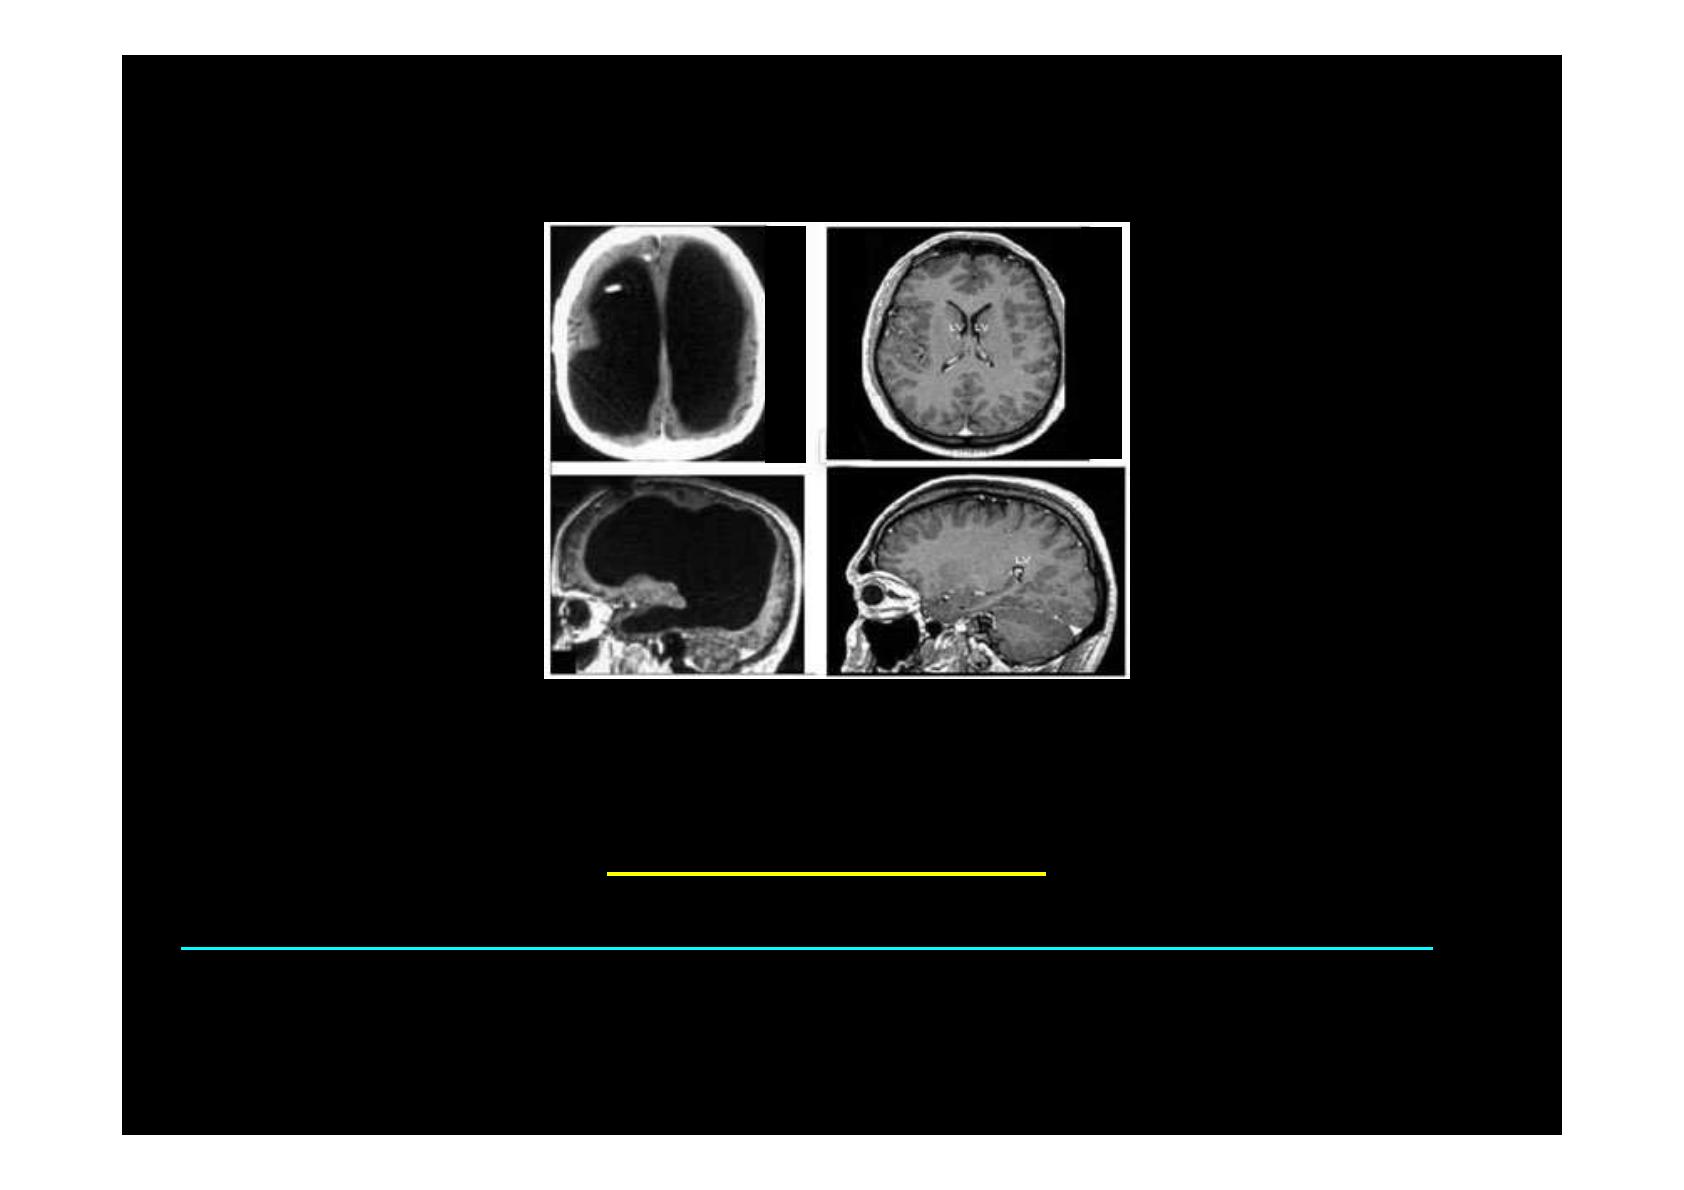

Homme : 44 ans, marié, 2 enfants, vie professionnelle normale

L. Feuillet et al, Lancet, 2007

Cerveau : mince couche aplatie sur les parois du crâne !!!

Aucune anomalie du fonctionnement du cerveau !